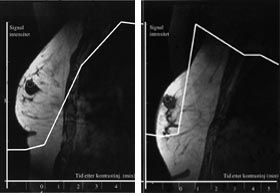

Generelt lader maligne brystkreftsvulster opp intravenøst injiserte MR-kontrastmidler raskere og kraftigere enn godartede svulster og normalt kjertelvev (fig 1). Dette har sammenheng med høyere vaskularitet og økt kapillærpermeabilitet i kreftsvulster sammenliknet med andre typer vev. Tidlige studier rapporterte at brystkreft ble diagnostisert med sensitivitet og spesifisitet på ca. 97 % når en økning i svulstens signalintensitet på 90 % eller mer i løpet av det første minuttet etter kontrastinjeksjon ble brukt som diagnostisk kriterium (11). Med økende erfaringsmateriale er det klart at også mange godartede lesjoner kan lade opp kontrastmiddel raskt og kraftig, særlig gjelder dette enkelte fibroadenomer, fibrocystisk dysplasi og skleroserende adenose (12). Spesifisiteten i senere kliniske MR-studier hvor pasientene har vært utvalgt på bakgrunn av mammografiske og kliniske funn har, avhengig av undersøkelsesteknikk og diagnostiske kriterier, variert fra 37 % til 89 % (13 – 17). Selv om enkelttilfeller av ikke-kontrastoppladende maligne brystvulster er rapportert (18), er den negative prediktive verdien av en MR-undersøkelse som ikke viser kontrastoppladende strukturer i brystet nær 100 %.